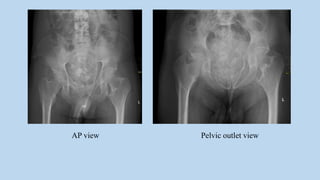

AP view Pelvic outlet view

AP view Pelvicoutlet view